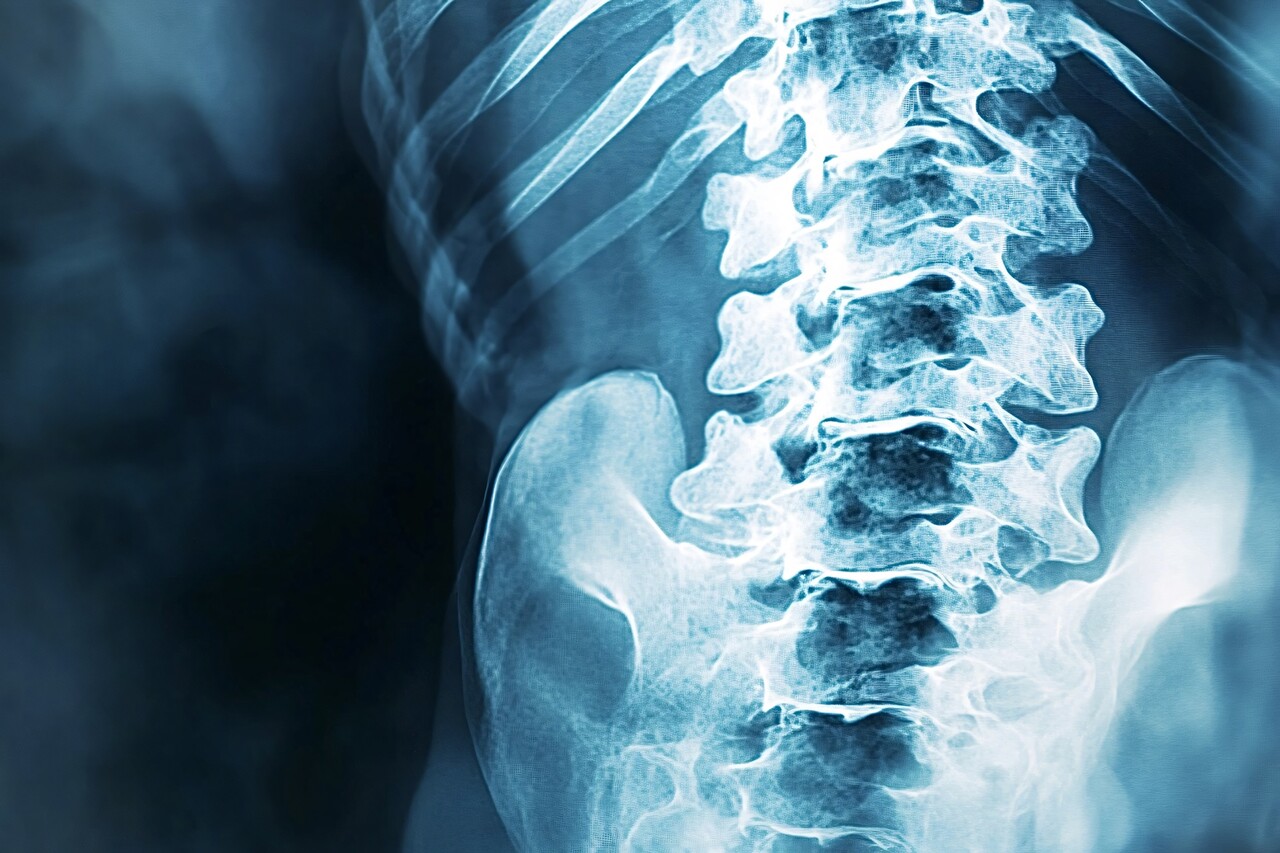

뼈 세포는 흔히 골형성 또는 뼈 리모델링 등으로 불리는 과정을 조절한다. 뼈 조직에 가해지는 물리적인 힘을 감지하고, 이에 따라 낡은 뼈 조직을 분해하고 새로운 뼈 조직을 만들 시점을 조절하는 방식이다.

이때 흔히 ‘노화 세포’라 불리는 것들이 문제가 된다. 노화된 뼈 세포는 더 이상 복제와 분열을 하지 않지만, 그렇다고 죽지는 않은 채 남아있는 세포를 말한다. 신체 다른 조직의 노화 세포와 마찬가지로, 세포의 정상적인 기능을 수행하지 않으면서 염증성 물질을 분비하는 손상된 세포다.

노화된 뼈 세포가 많아지면 리모델링이 둔해지면서 뼈 밀도가 감소한다. 이는 골다공증과 같은 뼈 질환 위험을 높인다. 해당 부위의 뼈 조직은 점점 탄성을 잃어 경직된 구조를 갖게 되며 점차 취약해진다.